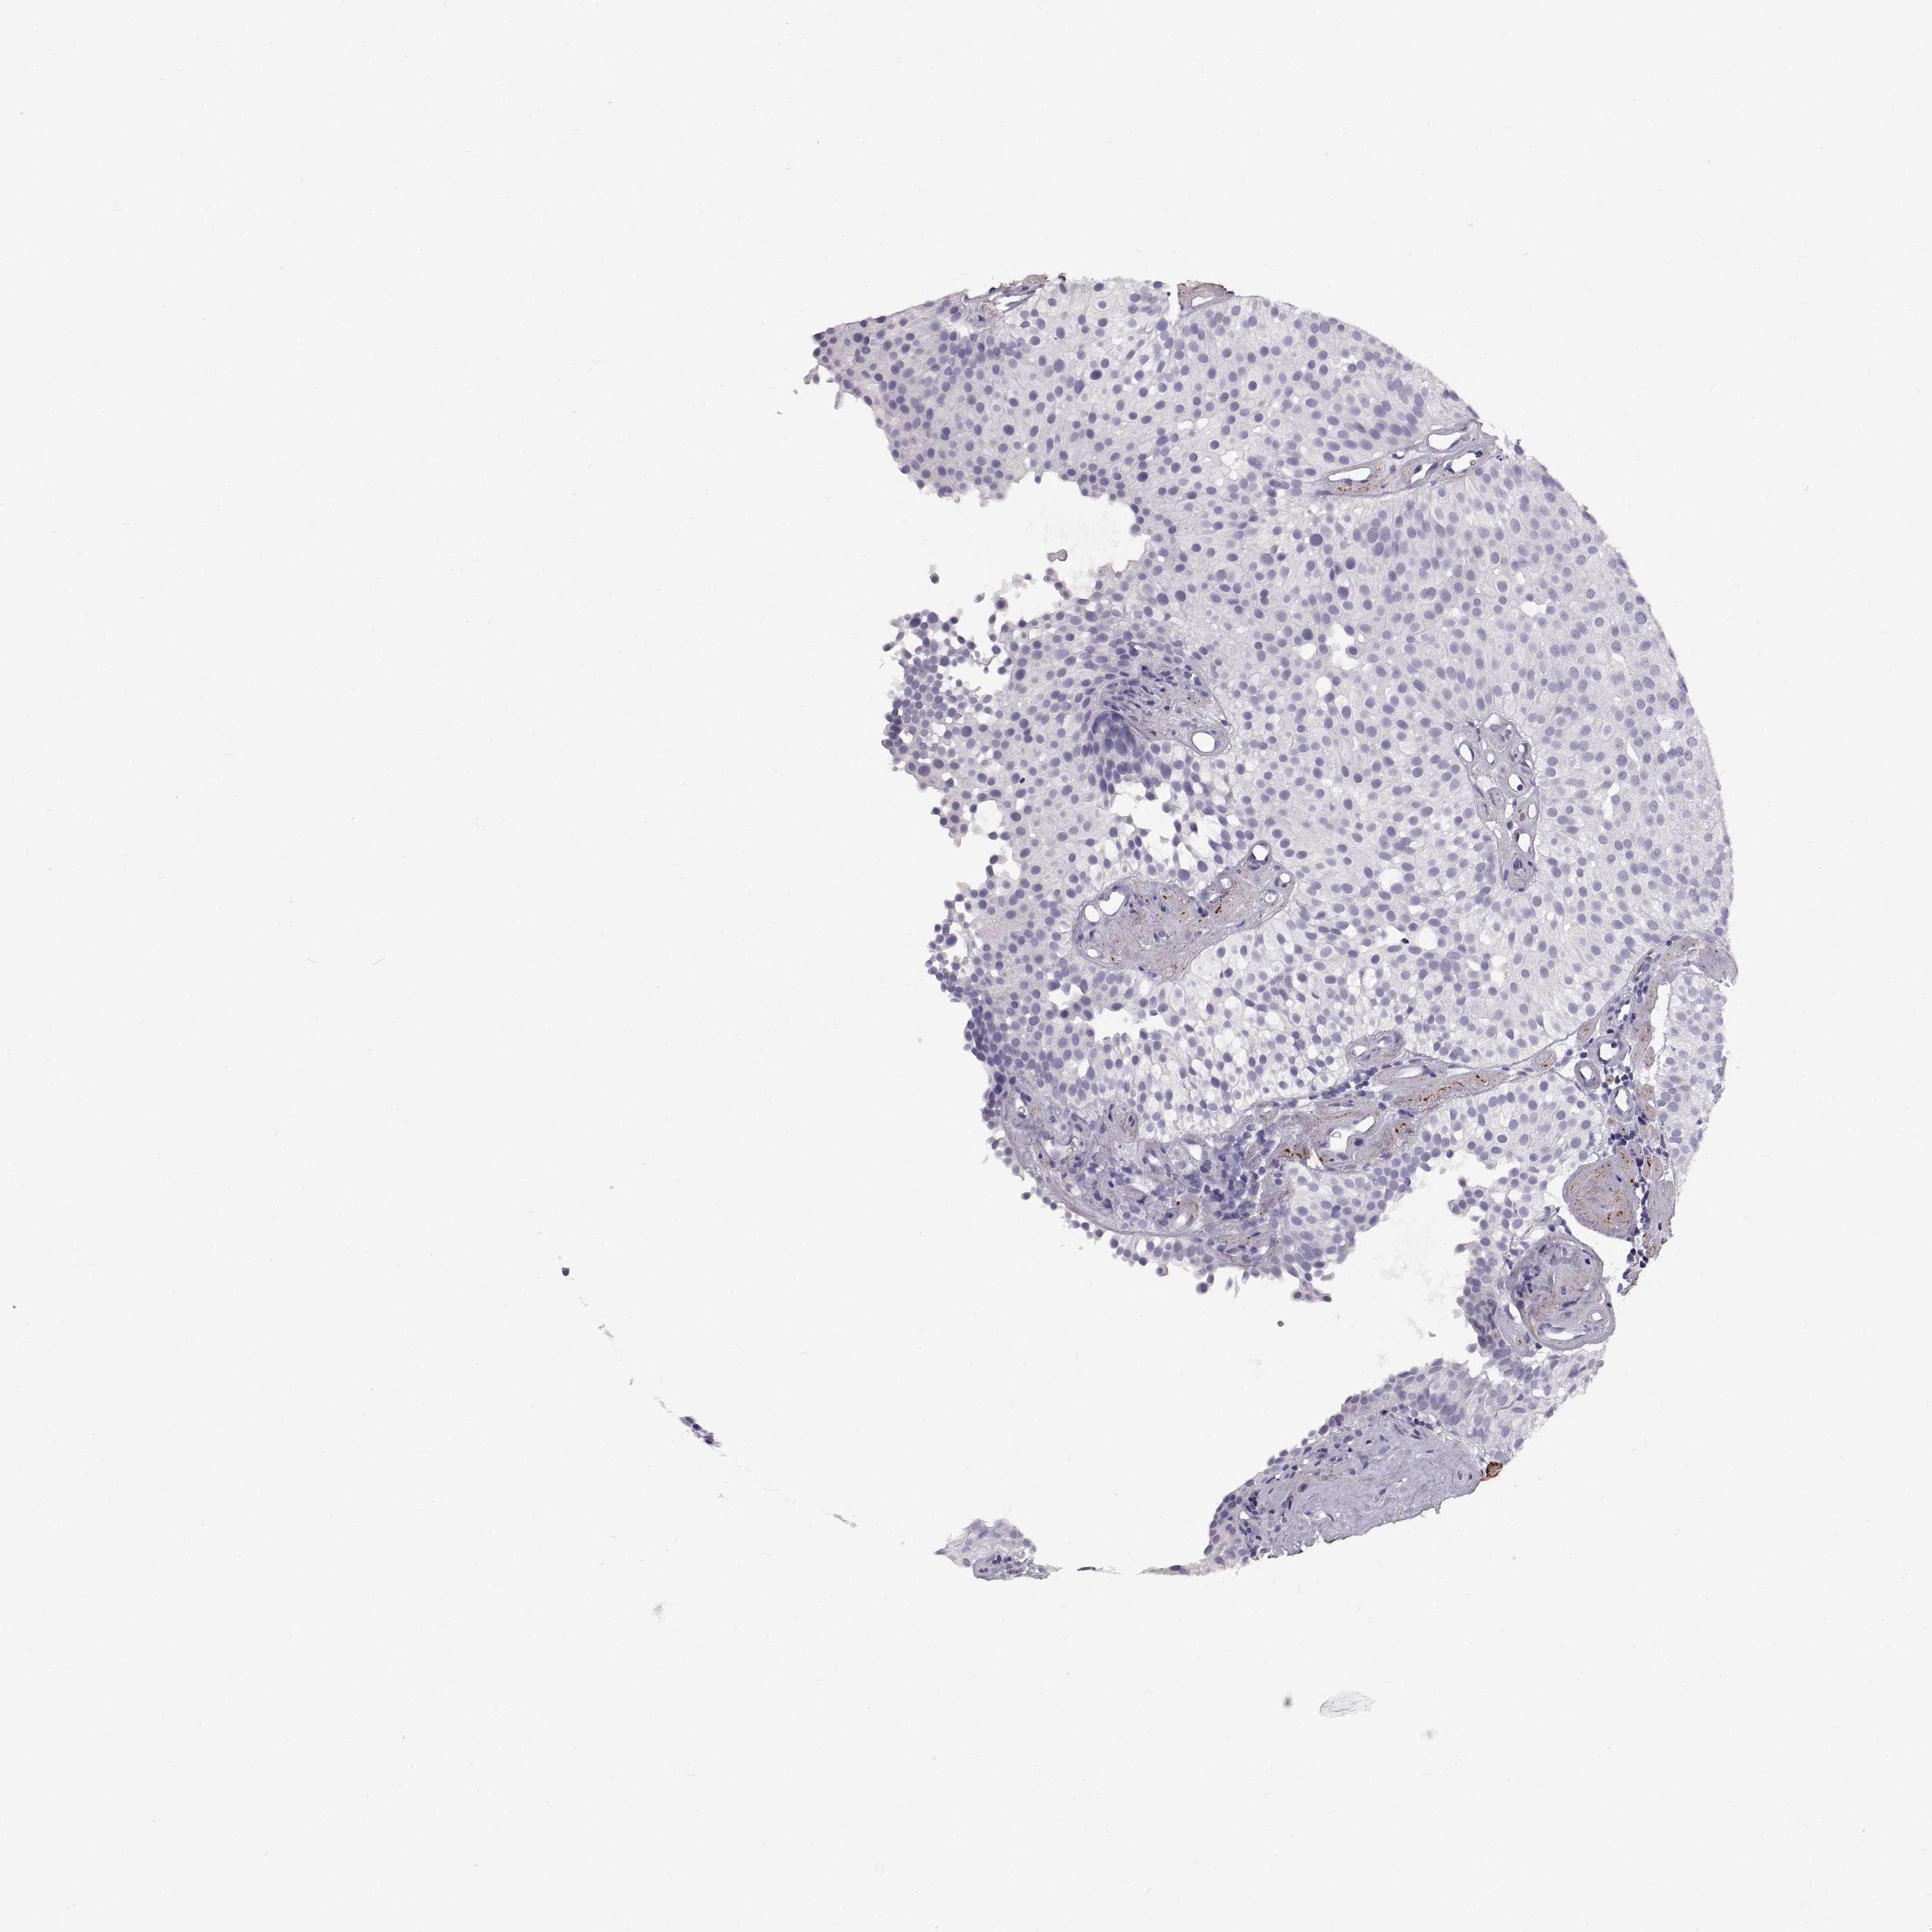

UROTHELIAL CANCER - Protein expressioni

A mouse-over function shows sample information and annotation data. Click on an image to view it in a full screen mode. Samples can be filtered based on level of antibody staining by selecting one or several of the following categories: high, medium, low and not detected. The assay and annotation is described here.

Note that samples used for immunohistochemistry by the Human Protein Atlas do not correspond to samples in the TCGA dataset.

Antibody stainingi

Antibody staining in the annotated cell types in the current human tissue is reported as not detected, low, medium, or high, based on conventional immunohistochemistry profiling in selected tissues. This score is based on the combination of the staining intensity and fraction of stained cells.

Each image is clickable and will lead to virtual microscopy that enables deeper exploration of all samples and also displays staining intensity scores, fraction scores and subcellular localization as well as patient and tissue information for each sample.

Antibody HPA070954

Staining

High

Medium

Low

Not detected

Intensity

Strong

Moderate

Weak

Negative

Quantity

>75%

75%-25%

<25%

None

Location

Nuclear

Cytoplasmic/membranous

Cytoplasmic/membranous,nuclear

Urothelial carcinoma, High grade

Urothelial carcinoma, NOS

Urothelial carcinoma, Low grade